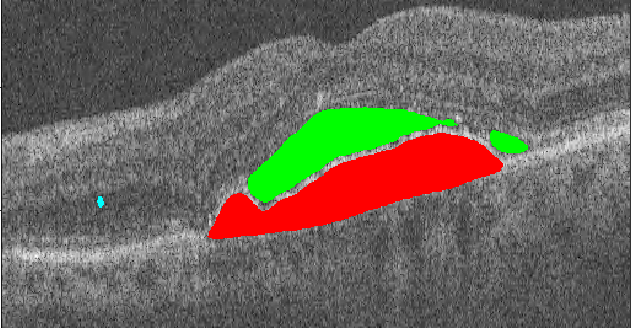

A deep learning model for segmentation of 13 features associated with neovascular and atrophic age-related macular degeneration (AMD).

Data for model development were obtained from 307 optical coherence tomography volumes. Eight experienced graders manually delineated all abnormalities in 2712 B-scans. A deep neural network was trained with these data to perform voxel-level segmentation of the 13 most common abnormalities (features). For evaluation, 112 B-scans from 112 patients with a diagnosis of neovascular AMD were annotated by 4 independent observers. The main outcome measures were Dice score, intraclass correlation coefficient, and free-response receiver operating characteristic curve.

On 11 of 13 features, the model obtained a mean Dice score of 0.63 ± 0.15, compared with 0.61 ± 0.17 for the observers. The mean intraclass correlation coefficient for the model was 0.66 ± 0.22, compared with 0.62 ± 0.21 for the observers. Two features were not evaluated quantitatively because of a lack of data. Free-response receiver operating characteristic analysis demonstrated that the model scored similar or higher sensitivity per false positives compared with the observers.